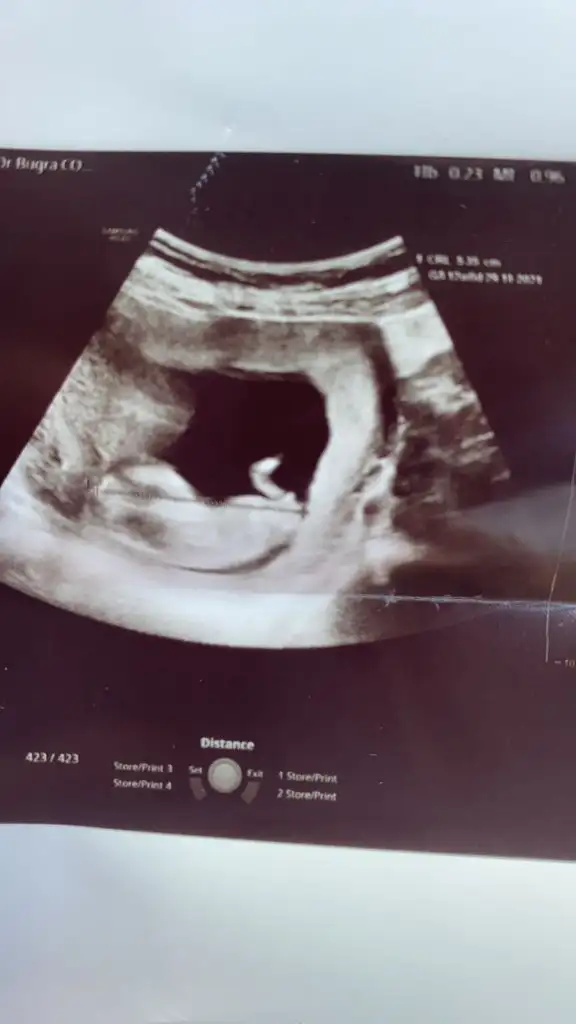

Ikra hanım merhaba 11+1den karından usg atıyorum rica etsem tahminde bulunur musunuz arkadaşım için bana kız demiştiniz doğru cıktı 🤭😊

Eklentiler

• IMG-20210515-WA0001.webp

IMG-20210515-WA0001.webp

33,8 KB · Görüntüleme: 62

• IMG-20210515-WA0002.webp

IMG-20210515-WA0002.webp

39,6 KB · Görüntüleme: 58

• IMG-20210515-WA0003.webp

IMG-20210515-WA0003.webp

26,5 KB · Görüntüleme: 69